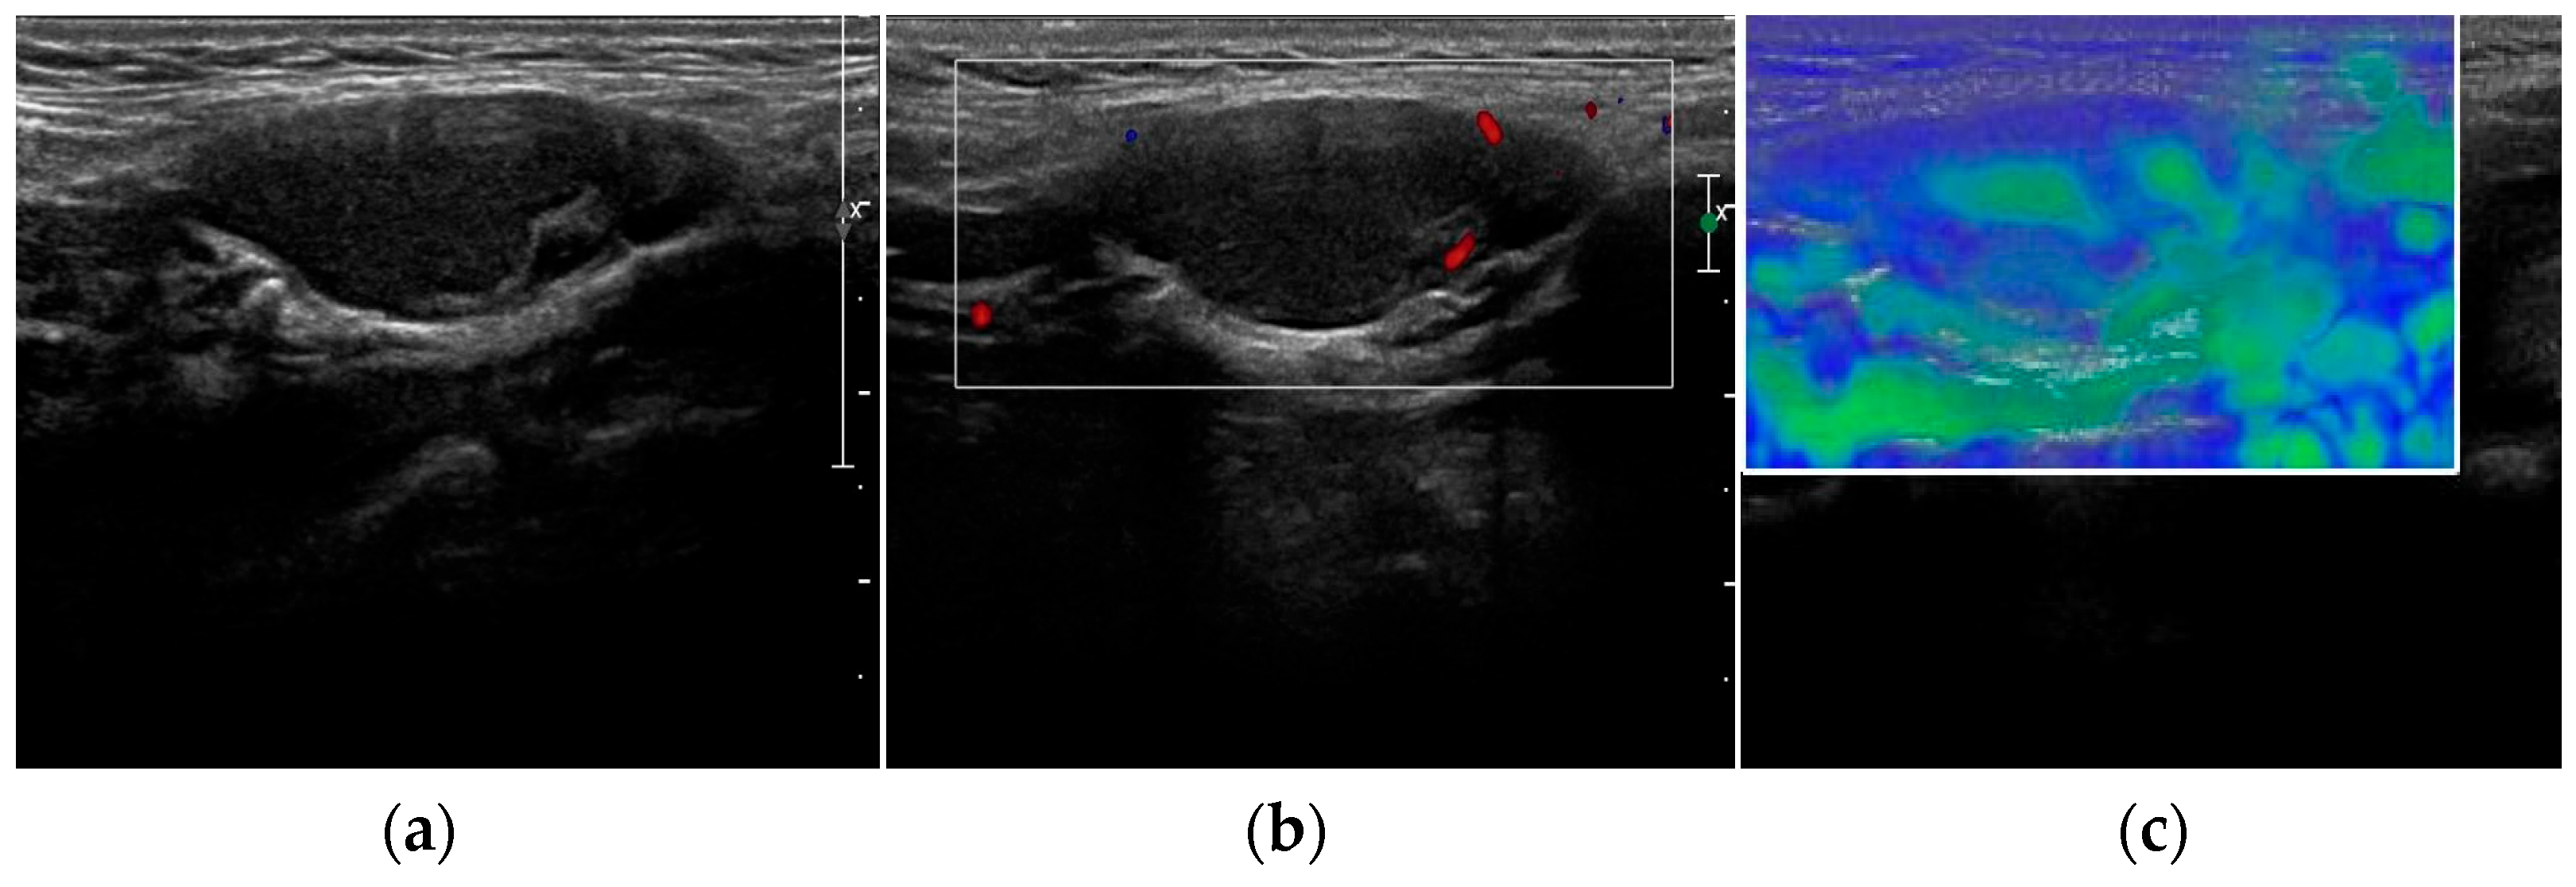

- Azizi, G.; Piper, K.; Keller, J.M.; Mayo, M.L.; Puett, D.; Earp, K.M.; Malchoff, C.D. Shear wave elastography and parathyroid adenoma: A new tool for diagnosing parathyroid adenomas. Eur. J. Radiol. 2016, 85, 1586–1593. [Google Scholar] [CrossRef]

- Isidori, A.M.; Cantisani, V.; Giannetta, E. Multiparametric ultrasonography and ultrasound elastography in the differentiation of parathyroid lesions from ectopic thyroid lesions or lymphadenopathies. Endocrine 2017, 57, 335–343. [Google Scholar] [CrossRef]

- Ünlütürk, U.; Erdoğan, M.F.; Demir, Ö.; Çulha, C.; Gullu, S.; Başkal, N. The role of ultrasound elastography in preoperative localization of parathyroid lesions: A new assisting method to preoperative parathyroid ultrasonography. Clin. Endocrinol. 2012, 76, 492–498. [Google Scholar] [CrossRef]

- Batur, A.; Atmaca, M.; Yavuz, A.; Ozgokce, M.; Bora, A.; Bulut, M.D.; Arslan, H.; Toktas, O.; Alpaslan, M. Ultrasound Elastography for Distinction Between Parathyroid Adenomas and Thyroid Nodules. J. Ultrasound. Med. 2016, 35, 1277–1282. [Google Scholar] [CrossRef]

- Chandramohan, A.; Therese, M.; Abhraham, D. Can ARFI elastography be used to differentiate parathyroid from thyroid lesions? J. Endocrinol. Invest. 2018, 41, 111–119. [Google Scholar] [CrossRef]

- Cotoi, L.; Borcan, F.; Sporea, I.; Amzar, D.; Schiller, O.; Schiller, A.; Dehelean, C.A.; Pop, G.N.; Stoian, D. Shear Wave Elastography in Diagnosing Secondary Hyperparathyroidism. Diagnostics 2019, 9, 213. [Google Scholar] [CrossRef]

| Parathyroid hyperplasia | More than one symmetrically or asymmetrically enlarged, hypoechoic, oval shaped, lobulated gland. Significantly smaller than adenoma. Cystic inclusions may be seen. | Feeding polar vessels entering the pole and then extending around the periphery. | Fast intense homogeneous enhancement. Fast homogeneous wash-out. | Stiffer than proper parathyroid glands. |

| Parathyroid adenoma | Enlarged, circumscribed, hypoechoic, oval shaped lesion, delineated by hyperechoic halo. Cystic inclusions may be seen. | Feeding polar vessels entering the pole and then extending around the periphery. | Early peripheral hyperenhancement. Central wash-out in the later phases. | Stiffer than hyperplastic parathyroid glands. |

| Parathyroid carcinoma | Length > 3 cm, depth/width ratio > 1. Lobulated, heterogeneous, hypoechoic lesion. Irregular borders. Thick capsule. Intranodular calcifications. Cystic inclusions may be seen. | Intralesional disordered vascularity. | Early heterogeneous enhancement. Early homogeneous wash-out. | Stiffer than proper, hyperplastic, and adenomatous parathyroid glands. |